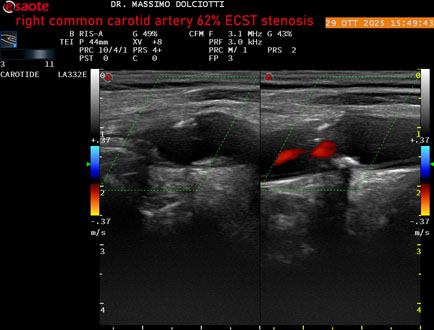

Data inserimento: 30/10/2025

Ecografia del: 29/10/2025

Strumento: Esaote MyLab Eight

Sonda: Lineare Multifrequenza 3-11 MHz

Età Paziente: F 75 anni

Motivazione dell'esame: controllo in pz con ateromasia carotidea ed ipercolesterolemia.

Commento all'esame: le immagini ed il video documentano all'arteria carotide comune destra placca disomogenea tipo 3 della classificazione di Gray Weale, che determina stenosi del 62% calcolato con metodo ECST.

Conclusioni: stenosi del 62% ECST dell'arteria carotide comune destra (62% ECST stenosis of the right common carotid artery).

Presentazione: Dr. Massimo Dolciotti - Ancona

Elaborazione digitale: Andrea Dini - Ancona